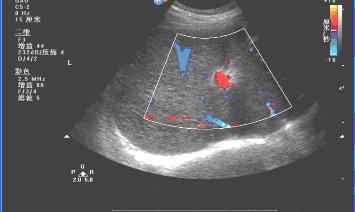

三、慢性肝炎肝硬化时的超声影像:

肝缩小,被膜不光滑,肝回声结节样增粗,门静脉扩张,腹水。